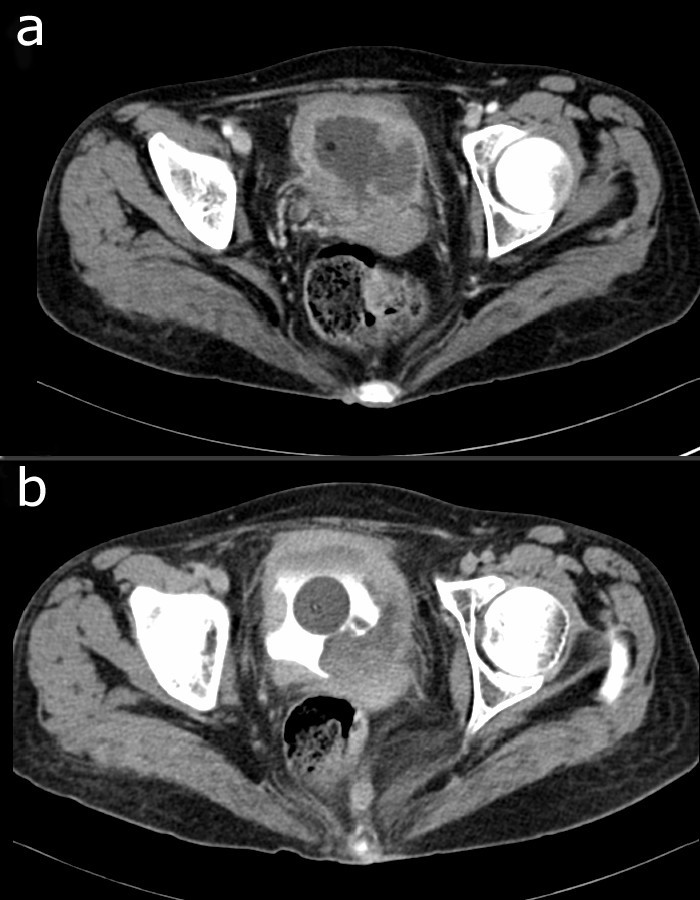

From www.researchgate.net

(PDF) Histological aspects of the bladder in systemic lupus erythematosus Lupus And Bladder Issues  Cns lupus can cause a number of issues, including confusion, brain fog (cognitive dysfunction), seizures, changes in personality,. Research from 2018 found that lupus commonly leads to urinary tract conditions, usually lupus nephritis. Yes, some autoimmune diseases like lupus and sjögren’s syndrome can also affect bladder function due to inflammation in various body. Although pelvic pain can be a symptom. Lupus And Bladder Issues.

(PDF) Bladder carcinoma in situ in a patient with Lupus cystitis Lupus And Bladder Issues  In this article, we will discuss six possible. Yes, some autoimmune diseases like lupus and sjögren’s syndrome can also affect bladder function due to inflammation in various body. Lupus nephritis occurs when lupus autoantibodies affect parts of the kidneys that filter out waste. Cns lupus can cause a number of issues, including confusion, brain fog (cognitive dysfunction), seizures, changes in. Lupus And Bladder Issues.

(PDF) Bladder involvement in systemic lupus erythematosus Lupus And Bladder Issues  Lupus nephritis occurs when lupus autoantibodies affect parts of the kidneys that filter out waste. Although pelvic pain can be a symptom of lupus, it can have other causes as well. Research from 2018 found that lupus commonly leads to urinary tract conditions, usually lupus nephritis. In this article, we will discuss six possible. Yes, some autoimmune diseases like lupus. Lupus And Bladder Issues.